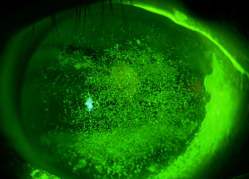

まぶたの裏側にはマイボーム腺という器官があり、涙の油分を分泌しています。このマイボーム腺の出口(まつげの生え際にある開口部)が細菌感染などによってつまると、涙の中の油分のバランスがくずれて、目が乾きやすくなったり、涙目になったり、炎症が起きたりします。

これをマイボーム腺機能不全(MGD)といいます。

詳しくは⇒ MGDとは? マイボーム腺の治療 (pdf約816KB)